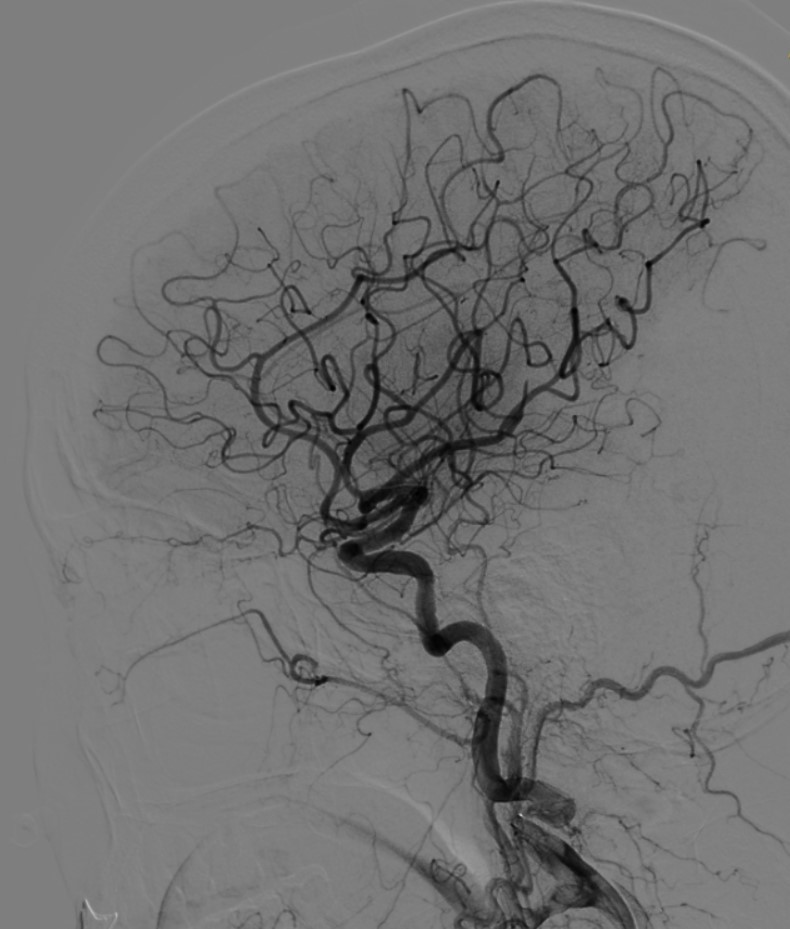

深夜的介入导管室内,陈洪乔副主任医师及其团队熟练操作,快速完成造影。造影见左侧颈内动脉栓塞,术中予支架拉栓+抽吸,抽出两块暗红色血栓,再次造影显示左侧颈内动脉完全再通。介入团队仅一次操作就成功开通闭塞的血管,从穿刺成功到完全再通仅40分钟。

完全再通的左侧颈内动脉